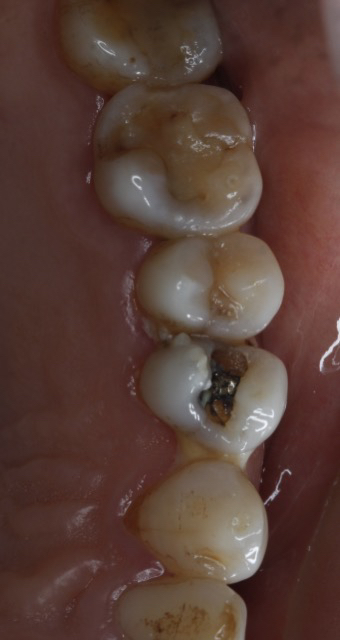

1. “不密合”是根源:银汞合金是金属,不会和牙齿产生化学粘结。时间长了,由于热胀冷缩或咀嚼力量,材料与牙齿之间会产生微小的缝隙。

2. “微渗漏”是通道:这条缝隙就成了细菌和食物残渣的“高速公路”,刷牙很难清洁到。细菌在此安家,久而久之,就从补牙材料的边缘开始,形成了新的蛀牙,这就是“继发性龋坏”。

当继发龋坏范围较大,或者原来的充填体已经不稳固时,简单的“重新补一下”可能不够牢固,容易再次脱落。这时,嵌体就是一个更优的选择。